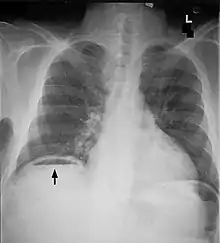

Free air under diaphragm seen on abdominal X-ray.

Abdominal free air

Bowel perforation presents with abdominal pain, free air in the abdomen on standing X-ray, and sepsis.[15][16][17] Depending on the cause and size, perforations may be medically or surgically managed. Some common causes of perforation are cancer, diverticulitis, and peptic ulcer disease.